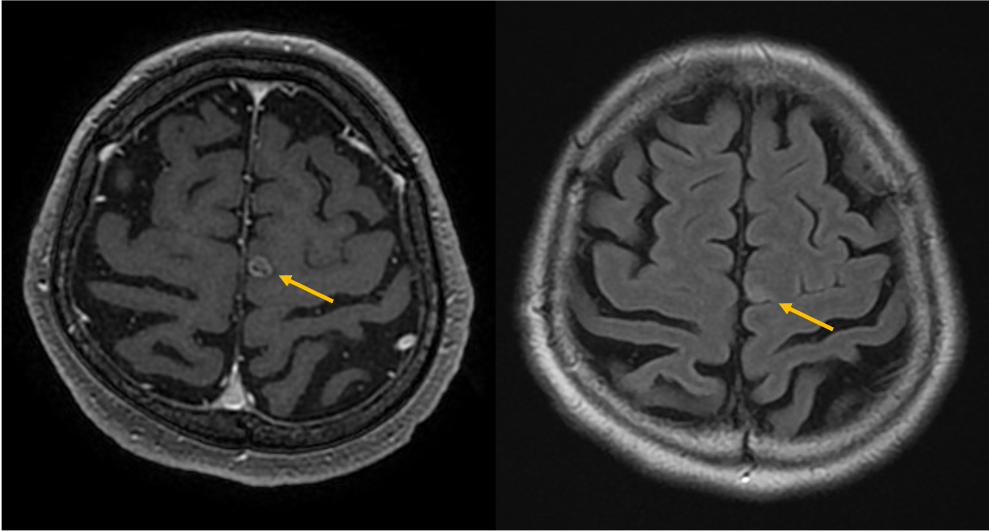

症例は70歳代男性。物が二重に見える、ふらつくとの訴えで来院。非造影MRIにて脳幹部や小脳に4個の多発脳腫瘍が認められ、症状と合致した。全身精査にて進行胃癌が発見され、その脳転移と診断された。放射線治療の適応判定のため造影MRIを施行し、新たに大脳に3個の微小転移が同定された。病変のサイズ・分布から微小転移を含む7個の腫瘍に対して定位放射線治療が可能と判断され、速やかに治療導入に至った。

本症例では先行する非造影MRIにて右中脳や左小脳の多発腫瘤が指摘され、周囲に浮腫を伴うことから転移が疑われていたが、病変数や大きさ・範囲ははっきりしなかった。造影MRIを実施することにより、右中脳に1個、左小脳に3個の2㎝大の輪郭の明瞭な腫瘍が確認されたほか、1㎝未満の3個の微小病変を新たに検出できた。非造影MRIを見直したところ7㎜の結節はFLAIRでも淡い高信号を示していたが質的診断は困難であった。3㎜の病変は非造影MRIでは存在診断不能であった。微小病変のうち2個は高位前頭葉の機能的に重要な部位に位置しており、治療適応と考えられた。造影MRIにより腫瘍の正確な個数とサイズ、分布の正確な情報を確認した後、定位放射線治療が可能と判断され、3D-FSPGR画像を治療計画に利用して迅速に治療が開始された。